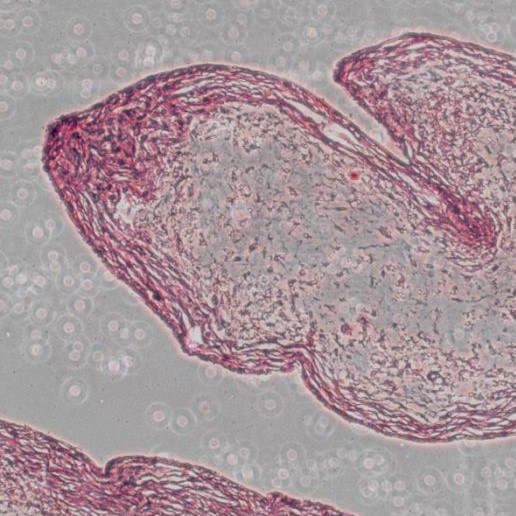

Four-reagent kit for identification of cartilage, mucins and mastocyte granules used in histology and cytology.